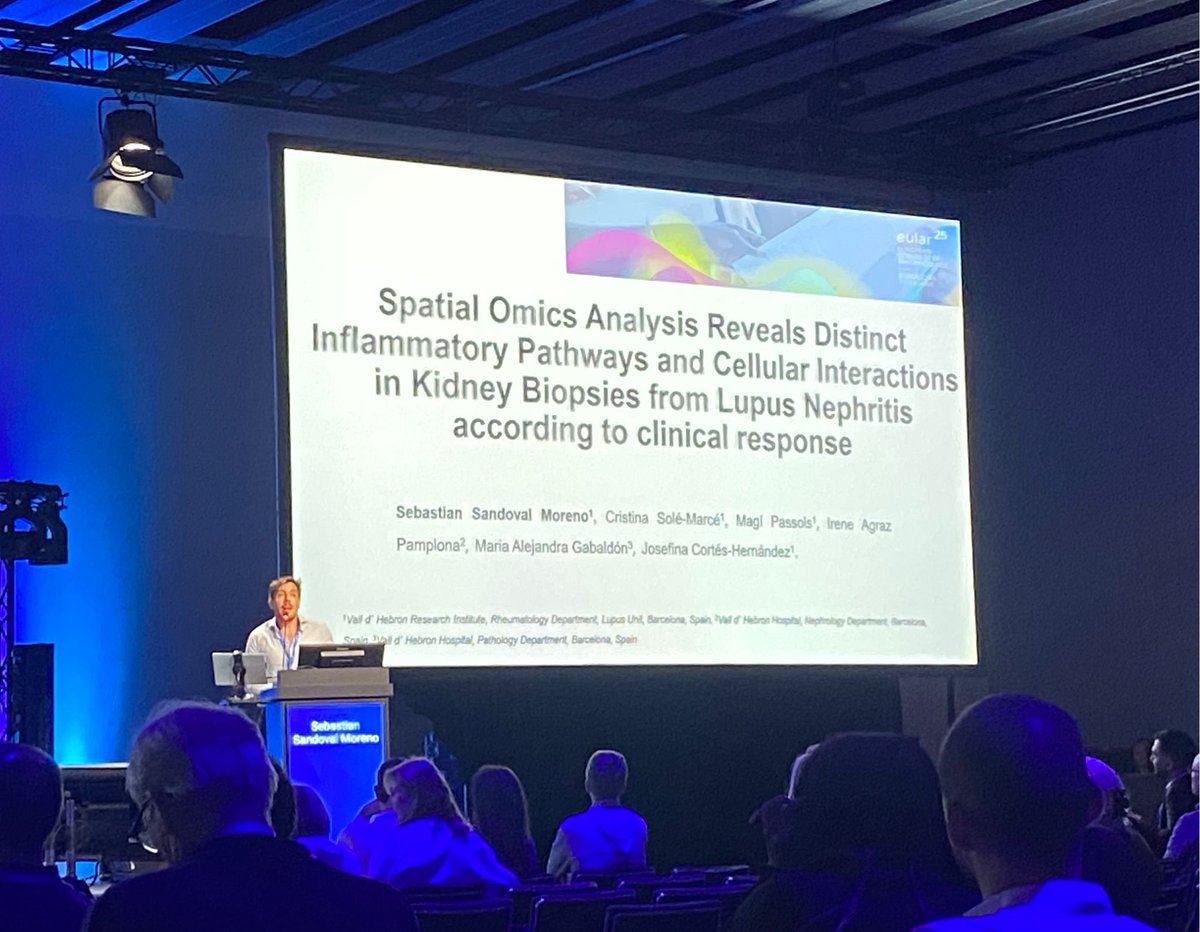

Nervios nervios! Increible comunicación oral de Sebastián Sandoval sobre transcriptómica espacial en biopsias renales de pacientes con lupus. Próxima tesis a la vista 👀 #EULAR2025 Reumatología Vall Hebron